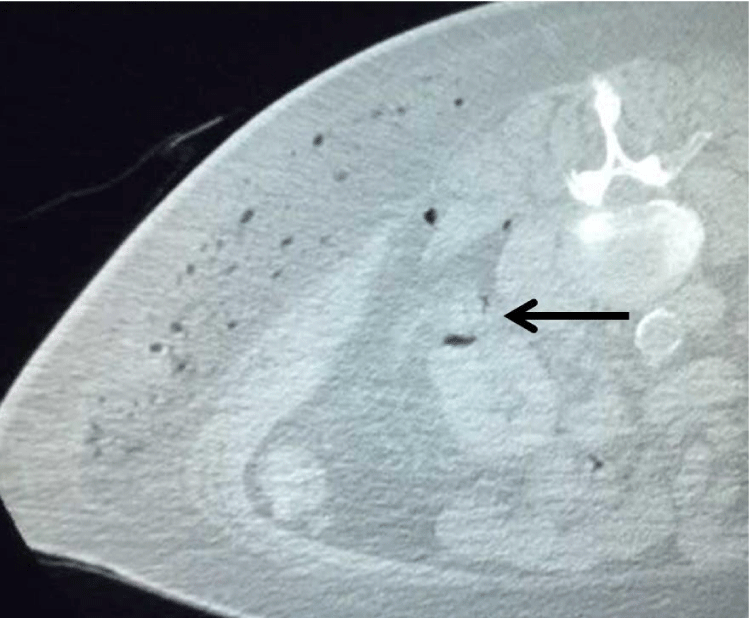

The patient is a 71 year old man with a history of a gastrointestinal stromal tumor (GIST) with s/ p tumor resection approximately three years prior to his presentation. A routine surveillance CT scan for his GIST tumor demonstrated a solid 1.8 cm exophytic left renal mass (Figure 1). After consultation with an urologist, the patient was scheduled for microwave ablation of the renal mass.

Figure 1: Axial CT scan of abdomen in a prone position shows an exophytic solid lesion (arrow; 1.7 cm in diameter, 46 Hounsfield units) arising from the left kidney.